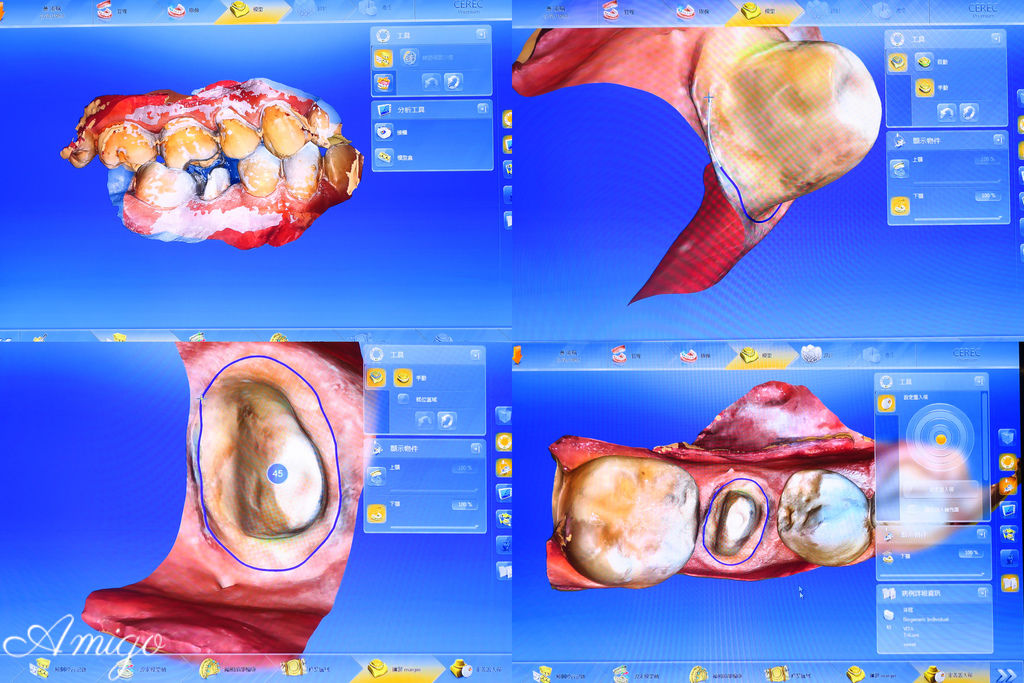

接著使用德國先進的全口3D全彩取像儀 來掃描口腔內的狀況

這個動作取代了傳統在患者口內做石膏灌模的程序

只需要張開嘴巴 不必侵入牙齒就能完成電子掃描

將口內牙齒狀況以3D彩色影像精準呈現在技師的工作螢幕上

技師在診間內即可使用全瓷假牙設計軟體預視患者的牙齒

由電腦運算製作假牙

只需透過電腦影像即可模擬調校出形狀大小似真牙的全瓷冠假牙

技師熟練迅速且精細地在畫面上調校曲線

為的就是待會可以磨出一顆精緻度極高的完美牙冠

電腦模疑出假牙完成的樣子

這時技師再次的進行修整

讓牙齒的弧度及咬合等方面更符合患者的使用需求

調整完後

便將假牙資訊傳送到下面這台德國VITA數位研磨機中